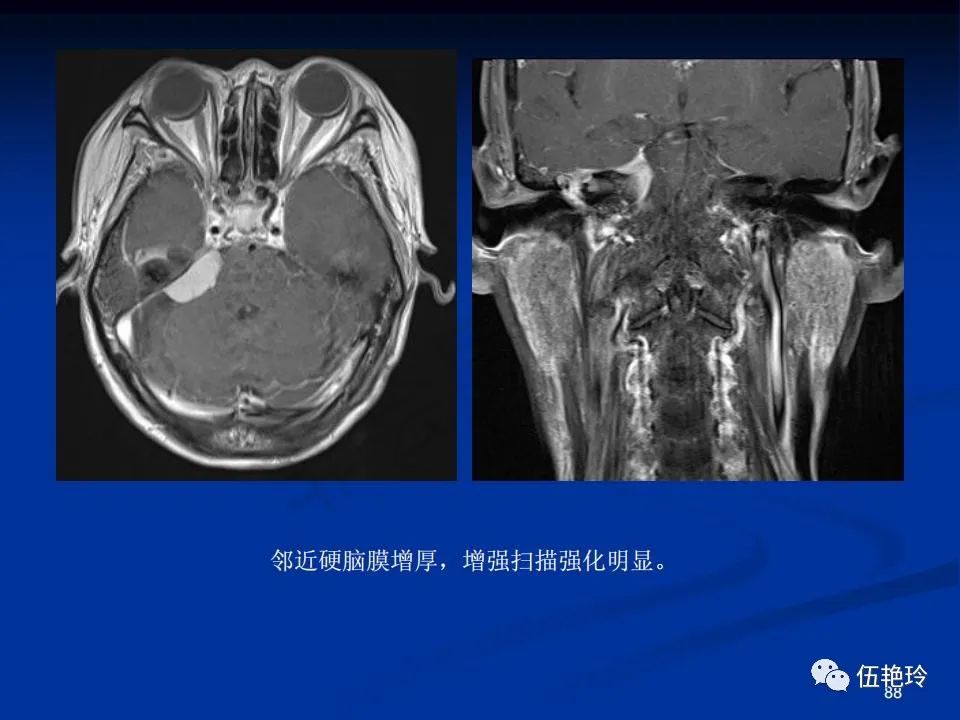

耳与面神经的解剖